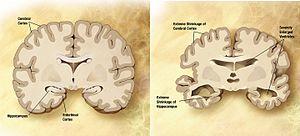

| Comparison of a normal aged brain (left) and the brain of a person with Alzheimer's (right). Characteristics that separate the two are pointed out. | |

Alzheimer's disease is characterised by loss of neurons and synapses in the cerebral cortex and certain subcortical regions. This loss results in gross atrophy of the affected regions, including degeneration in the temporal lobe and parietal lobe, and parts of the frontal cortex and cingulate gyrus.[55] Degeneration is also present in brainstem nuclei like the locus coeruleus.[88] Studies using MRI and PET have documented reductions in the size of specific brain regions in people with AD as they progressed from mild cognitive impairment to Alzheimer's disease, and in comparison with similar images from healthy older adults.[89][90]

Both amyloid plaques and neurofibrillary tangles are clearly visible by microscopy in brains of those afflicted by AD.[91] Plaques are dense, mostly insoluble deposits of beta-amyloid peptide and cellular material outside and around neurons. Tangles (neurofibrillary tangles) are aggregates of the microtubule-associated protein tau which has become hyperphosphorylated and accumulate inside the cells themselves. Although many older individuals develop some plaques and tangles as a consequence of ageing, the brains of people with AD have a greater number of them in specific brain regions such as the temporal lobe.[92] Lewy bodies are not rare in the brains of people with AD.[93]